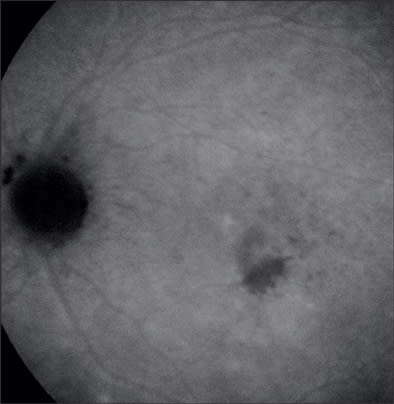

On initial exam, his vision was 20/25 in both eyes, anterior segment was benign and there was no evidence of vitreal cell. Inferiotemporal to the fovea of his left eye, he had a hypopigmented lesion deep to the retinal vessels (Figures 1A and 1B). On fluorescein angiography (FA), the hypofluorescent lesion appeared to be a cluster of hyperfluorescent dots (Figure 2), which were more apparent than on clinical examination. These dots appeared to stain slightly during late-phase angiography (Figure 3). Early-phase indocyanine green angiography (ICG) was unremarkable; however, during late-phase angiography, there were small hypofluorescent dots overlying larger hypofluorescent spots (Figure 4). There was also a lacy, irregular ring of hypofluorescence at the margin of the optic disc. The hypofluorescent spots appeared more numerous than was apparent on either fluorescein or on clinical exam. Microperimetry was performed. The imaged blind spots on microperimetry (Figure 5) corresponded to the hypopigmented areas noted on ICG. One week after the initial visit, multiple hyperfluorescent white dots appeared on the FA (Figure 6); during this visit, the patient had vitritis that resolved spontaneously within a few days. Repeat microperimetry (Figure 7A) and ICG (Figure 7B) showed improvement 6 weeks after the initial visit and after a course of steroids. Imaging supports a diagnosis of multiple evanescent white dot syndrome (MEWDS). RP

Figure 1A. Fundus photo showing clinically apparent hypopigmented lesion (initial visit).

Figure 1B. Red-free photo of the lesion (initial visit).